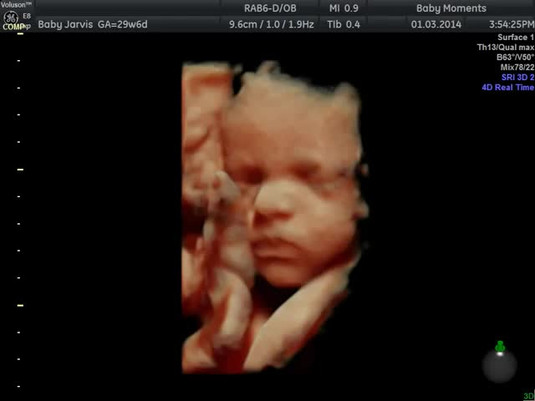

Phòng Khám Phụ Khoa Bác Sĩ Chánh